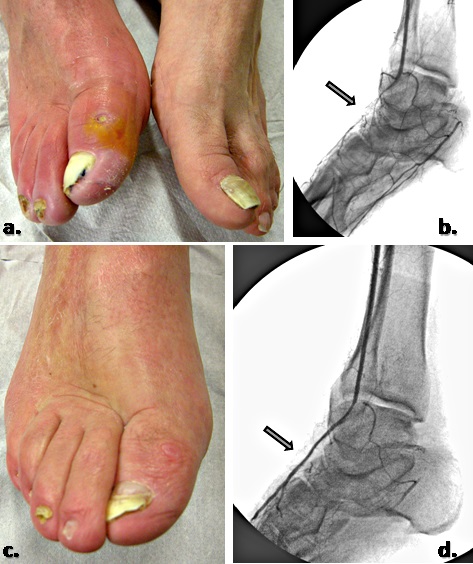

علائم زخم ایسکمی

تغییرات پوستی: پوست اطراف زخم ممکن است رنگ پریده، تاریک یا تغییر رنگ به نظر برسد. در برخی موارد، ممکن است پوست هنگام لمس نیز خنک شود.

تأخیر در بهبود زخم: زخم های ایسکمیک معمولاً به آهستگی بهبود می یابند یا ممکن است به دلیل اختلال در جریان خون در ناحیه، اصلاً بهبود نیابند که منجر به زخم های باز مداوم می شود.

ظاهر زخم: زخم های ایسکمیک اغلب دارای مرز مشخصی هستند و ممکن است به صورت زخم های کم عمق یا عمیق با پایه ای از بافت نکروزه (مرده) ظاهر شوند.

افزایش خطر عفونت: به دلیل جریان خون به خطر افتاده و آسیب بافتی، زخم های ایسکمیک در معرض خطر بیشتری برای عفونی شدن هستند، که می تواند بهبود را بیشتر به تاخیر بیاندازد و منجر به عوارض شود.